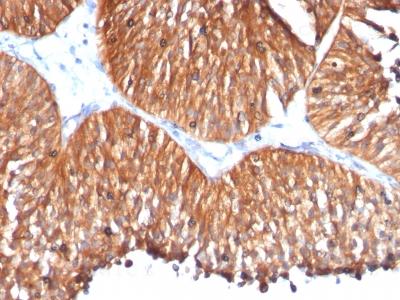

Monoclonal Antibody to HSP60 (Heat Shock Protein 60) (Mitochondrial Marker)(Clone : HSPD1/780)

Formalin-fixed, paraffin-embedded human Bladder Carcinoma stained with HSP60 Monoclonal Antibody (HSPD1/780)